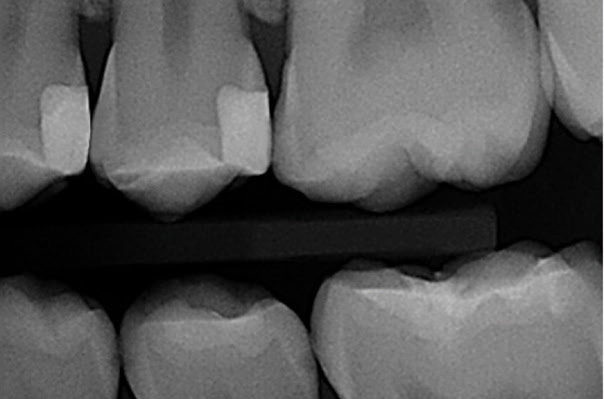

Both preparations were isolated with the X5 system by first placing the metal matrix, the wedge, and then the ring. (Figure 3) The teeth were restored using a selective etch bonding technique, universal composite, and LED curing light. After removing the X5 components the restorations were adjusted with a fluted carbide finishing bur and proper occlusion was verified. (Figure 4) Finally, during a follow-up hygiene exam the completed restorations on teeth Nos. 12 and 13 are visualized and showed excellent interproximal contact and contour. (Figure 5)

- Figure 5: Post-operative bitewing radiograph showing excellent interproximal contour and contact.